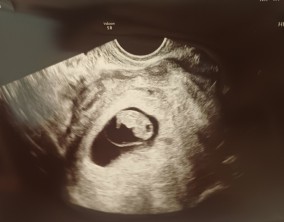

조심스러운 기쁨이 안도가 되기까지

이유정 원장님께서 차분하고 사실적으로 치료 과정과 정보를 설명해 주셔서 불안한 마음이 많이 줄어들었습니다. 미디어에서 접했던 이야기들로 걱정이 컸던 만큼, 현실적인 설명…